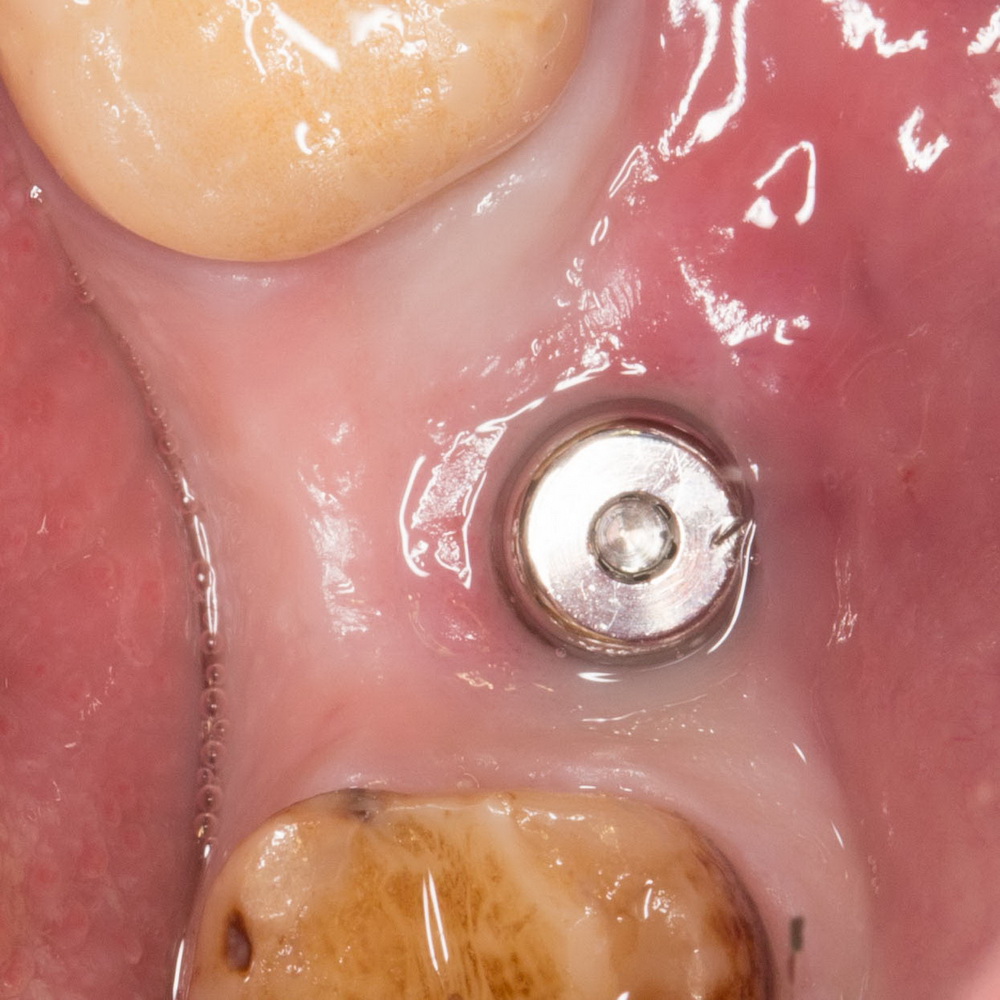

Если имплантат установлен одномоментно с формирователем десны, то при перкуссии он безболезненный. Появление боли при надавливании на формирователь говорит о том, что импланту совсем плохо и он, с высокой степенью вероятности, не интегрируется. При этом, на рентгеновских снимках не будет никаких видимых изменений. Иногда даже сильной подвижности импланта нет.

Если имплантат полностью находится под десной, пациента может беспокоить отек слизистой, формирование свищей и неприятные ощущения в области операции. Если данные явления не проходят и после снятия швов — имеет смысл провести санацию раны, проверить, всё ли в порядке с имплантами (иногда бывает, что неприятные ощущения и образование свищей вызывает недозакрученная заглушка импланта — и это не повод удалять имплантат, можно просто поменять заглушку).

Еще одним симптомом развивающейся проблемы является появление излишней подвижности импланта. Конечно существуют имплантационные системы, которые не предполагают первичной стабильности (например, тот же Bicon или Ankylos), но если после одномоментной установки коронки или формирователя десны появилась подвижность, которой изначально не было, да еще и она болезненна — имплантат, стопроцентно, кандидат на удаление.